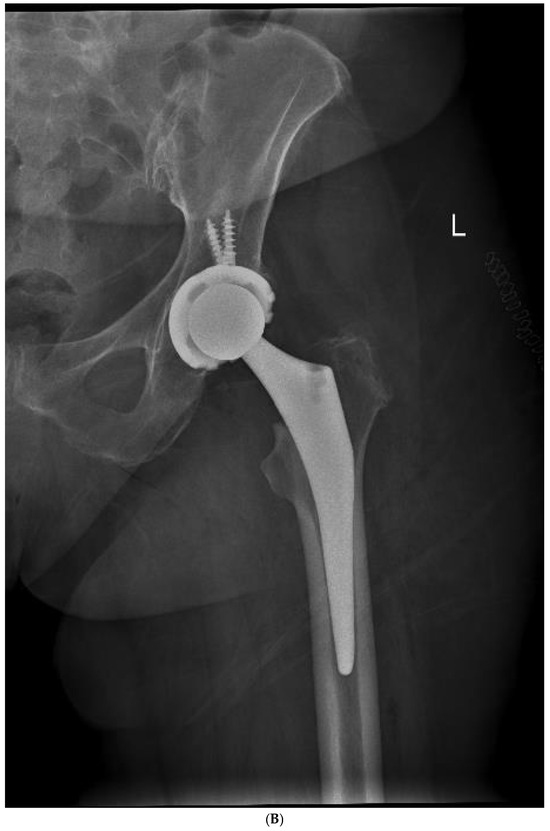

The average cup inclination and anteversion were 43° ± 3° (range, 38–50°) and 10° (range, 0–15°), respectively, in the SFS group, compared with 44° ± 5° (range, 37–50°) and 5° (range, 3–15°) in the CSS group. All acetabular components were positioned within Lewinnek’s safe zone. No radiolucent lines, cup migration, or broken screws were observed in either group throughout the follow-up period. Radiographic signs of osseointegration were present in all implants, with at least three of Moore’s criteria met in every SFS case (Figure 3A–C), indicating complete osseointegration. Similar findings were noted in the CSS group (Figure 4A–C). No femoral radiolucency or periprosthetic osteolysis was detected at any scheduled follow-up. Stem subsidence of approximately 3 mm was observed at the 3-month follow-up in two hips in the SFS group and three hips in the CSS group; however, these cases were not associated with clinical symptoms or functional impairment. No femoral stem loosening was identified during the follow-up period. A leg length discrepancy (LLD) of less than 1 cm was observed in three hips in the SFS group (average, 4 ± 3 mm) and in eight hips in the CSS group (average, 4 ± 5 mm). None of these discrepancies resulted in clinical or functional complaints, and no heterotopic ossification was identified in the radiographic evaluations (Table 4).

Figure 4.

(A) Preoperative anteroposterior X-ray. Left hip sustained a displaced femoral neck fracture. (B) Postoperative anteroposterior X-ray (CSS group). Femoral stem shows osseointegration and good proximal loading, with no bone resorption at final follow-up. (C) Postoperative lateral X-ray (CSS group). At final follow-up, the stem shows no subsidence and good fixation.